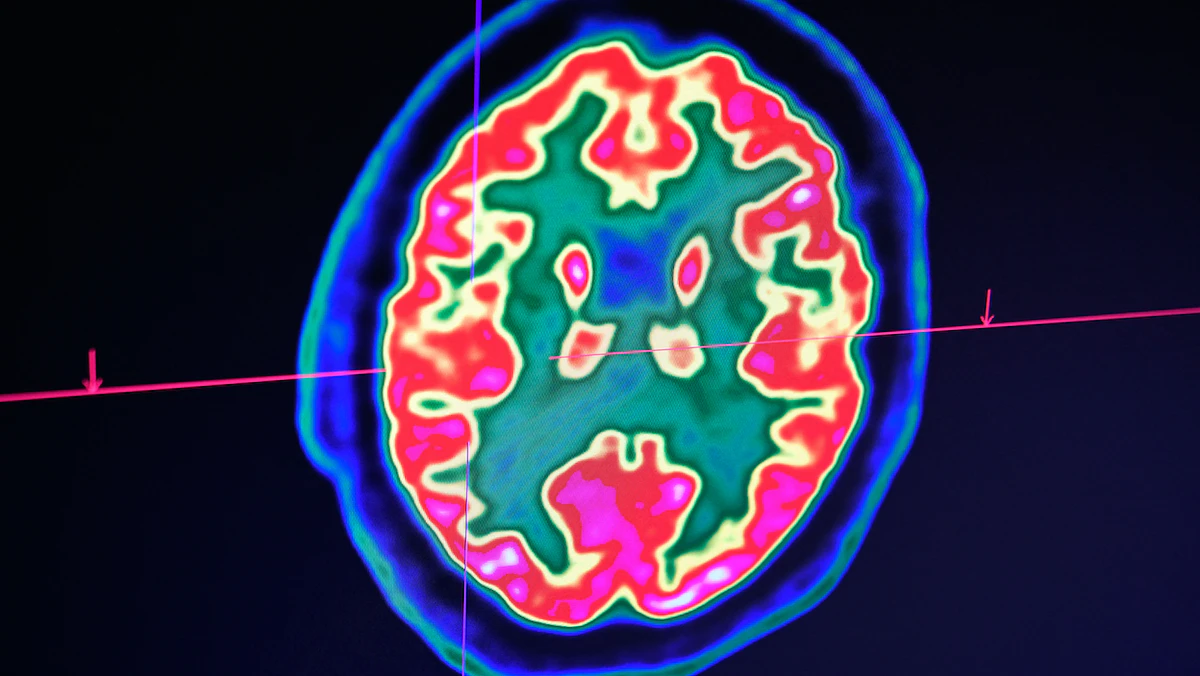

واستخدم الباحثون الرنين المغناطيسي الوظيفي في الدراسة لرصد الإشارات التي تخرج من منطقة المكافأة في الدماغ، والتحكم المعرفي والمرتبطة بقشرة الفص الجبهي، ووجدوا أن تلك المناطق تنشط بشكل أكبر كلما زادت فترة سلوكيات تفقد من وسائل التواصل الاجتماعي.

كما أظهرت مناطق في الدماغ اختلافات في النشاط العصبي طبقاً لعدد الساعات التي ينشطون فيها على مواقع التواصل الاجتماعي.